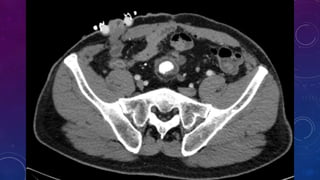

• Multiple pelvic phleboliths.

• Small well-defined round osseous lesions in the left

side of the abdomen, adjacent to midline represent

calcified lymph node in the para-aortic and left

common iliac groups, also visualized on the

corresponding CT.

WHERE?

PROSTATIC CALCIFICATION

PRE RENAL TRANSPLANT EVALUATION.